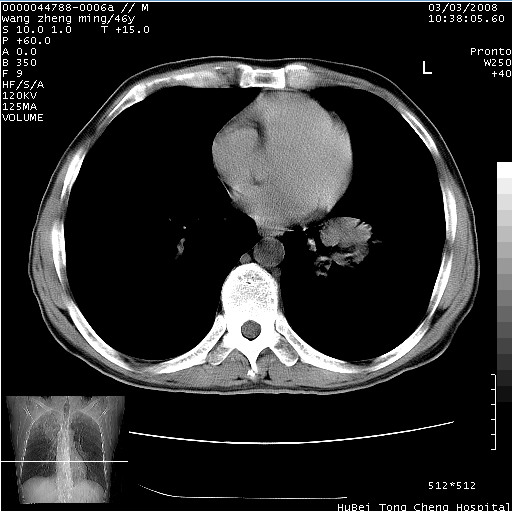

以下是引用卜一在2008-3-22 1:37:00的发言:[br]右肺实质性肿块,边缘不整,明显见毛刺征 分叶征及胸膜凹陷征,右上叶支气管明显变窄,远端散在的片状 斑片状实变影。另:左肺门较大肿块,支气管受累 变窄,远侧见阻塞性肺炎。纵隔内见肿大淋巴结。多考虑:右肺周围性肺癌伴左肺门 纵隔淋巴结转移!